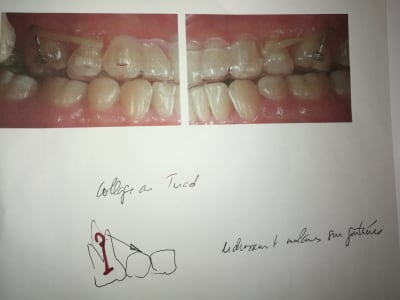

Ici le patient à besoin d'un traitement complet mais j'ai un soucie, la 46 est absente et la 47 versé et à une rotation.

Un cas qui montre la séquence

Ouverture d'espace en deux mois environ, straight wire avec un ressort. C'est con simple , efficace et relativement comfortable pour le patient

Finition de la position de la 7 après la pose de l'implant en utilisant une bague sur la provisoire.

Et le patient deux mois plus tard.

Encore un petit mois et l'on devrait pouvoir poser l'implant.

Bien géré le redressement de la 47 .